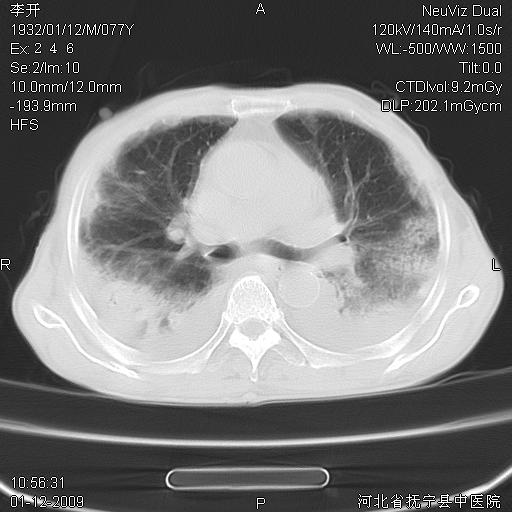

以下是引用黑白光影在2009-1-19 16:49:00的发言:[br]心衰肺水肿;心包、胸腔积液;冠脉钙化;肺部感染。